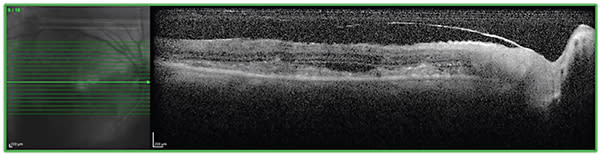

On dilated examination, her right fundus demonstrated a dense vitritis, preretinal hemorrhages, a swollen optic disc and a creamy white subretinal lesion along the inferior arcade (Figure 1A). Her left eye examination was unremarkable (Figure 1B). Fluorescein angiography of her right eye revealed peripapillary leakage and diffuse leakage along the subretinal lesion and inferior arcade (Figure 2A). Furthermore, there were hyperfluorescent foci inferior to the macula (Figure 2B). Spectral-domain optical coherence tomography (SD-OCT) demonstrated hyper-reflective subretinal material (Figure 3). Given the broad differential for her presentation of posterior uveitis, initial management thus consisted of empirical treatment with oral trimethoprim-sulfamethoxazole, acyclovir and voriconazole. We obtained infectious and inflammatory labs and diagnostic paracentesis of anterior chamber fluid and vitreous fluid, all of which were unrevealing.

Figure 3. SD-OCT of the right eye demonstrates hyper-reflective subretinal material.